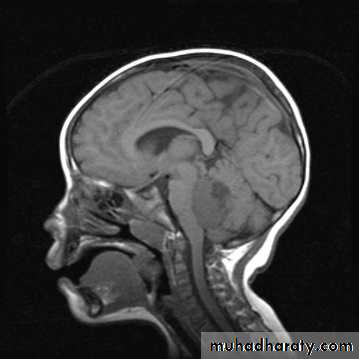

MRIBrain Tumors of Childhood

Histogenesis:* Cell of origin:

glial, neural, primitive, choroid, mixed

* Location:

posterior fossa: 70%

supratentorial: 30%

* Clinical presentation:

location

age

type and grade of the tumor

Symptoms may include:

Increased intracranial pressuresecondary to obstruction of CSF at aqueduct

hydrocephalus (infants), headache, papilledema, vomiting

seizures

focal neurological deficits

hormonal changes (pituitary adenoma)

visual changes (diplopia, field defects)

pressure on optic chiasm